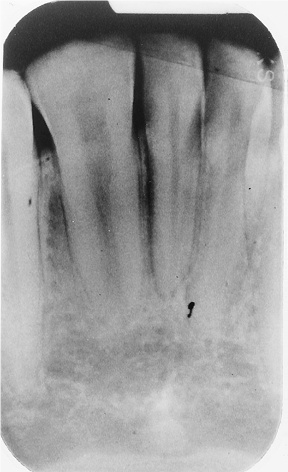

The radiograph shows evidence of

3 / 30

3. (Select ONE OR MORE correct answers)